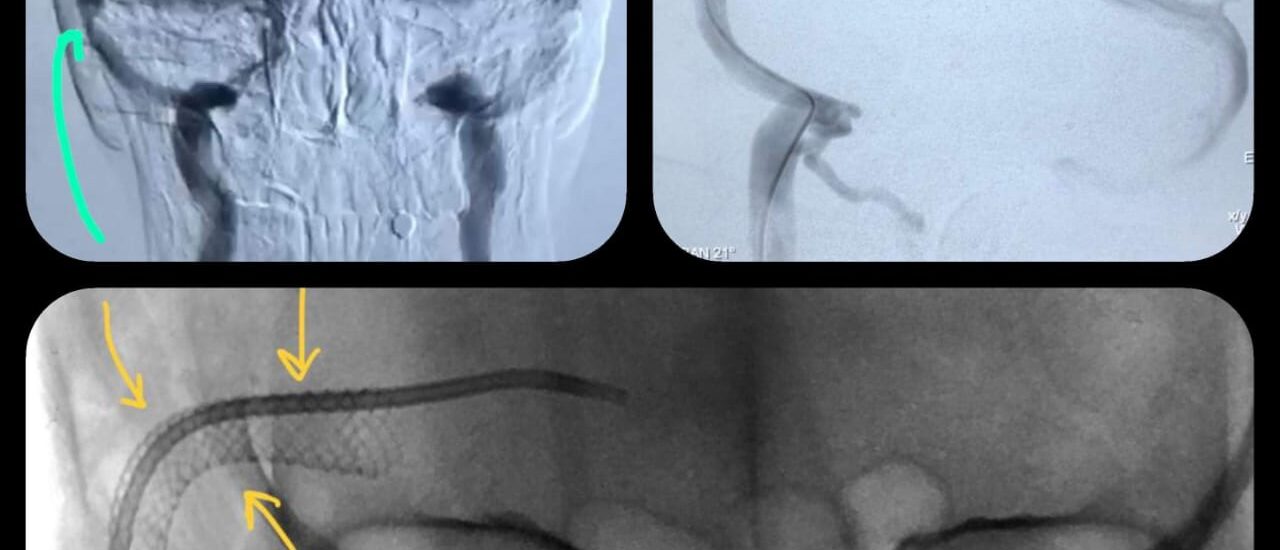

Correction of Congenital sharp angular kyphosis

Female pt 14 yrs, complaining from back pain due to congenital sharp angular kyphosis otherwise there wasn’t any neurological deficit Pre-op X-ray 3D Reconstruction Surgical planing for vertebral column resection of the apical vertebra using surgimap program for accurate correction according to Sagittal balance parameters…